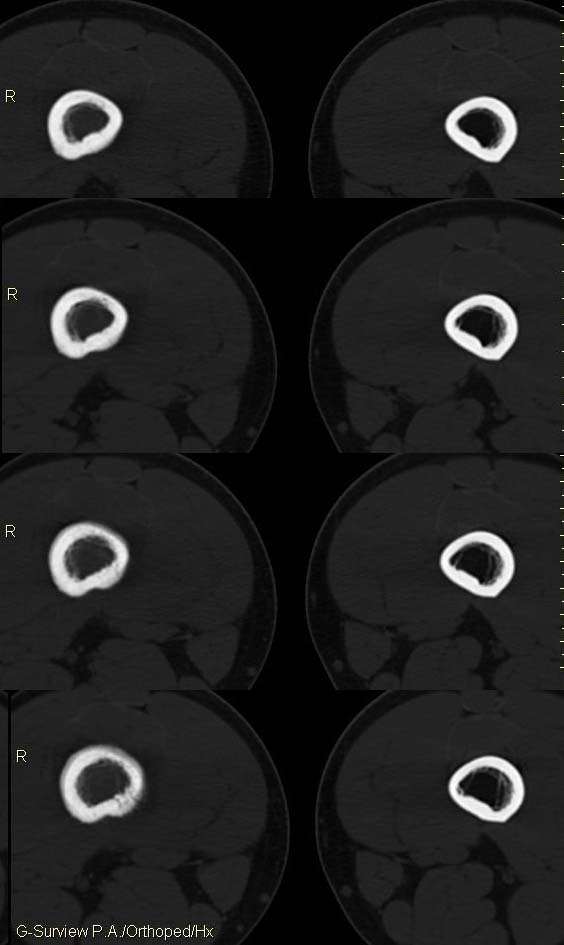

20岁,男,右股骨下端疼痛一个月,无发热,白细胞正常,皮肤不红,肿胀,触痛。

右股骨下端很长范围内的髓腔扩大,骨小梁破坏消失,皮质亦呈融骨性破坏,周围脂肪层次紊乱,肌肉受累及密度减低。考虑为:恶性骨肿瘤。请专家们分析骨肉瘤及尤文氏肉瘤的ct征象。

6.ct及mri:能较好地判断肿瘤的范围及侵犯软组织的情况。mri可见瘤体处广泛性骨质破坏,呈软组织肿块影;在t1加权像上呈均匀的长t1信号;在t2加权像上呈很长t2高信号。在ct上显示为源于骨组织的软组织肿块,骨质广泛破坏。

长骨ct见的较少,该病例股骨下端表现为边缘模糊的溶骨性破坏,伴有费用性脱钙,髓腔密度增高,呈毛玻璃样改变,病变周围软组织肿胀,脂肪间隙模糊,无骨膜反应,应密切结合临床,考虑骨纤维肉瘤或慢性骨脓肿。期待结果。

此病例基本可定是恶性骨肿瘤:髓腔内长范围肿块、皮质不规则破坏、软块及软组织浸润、瘤骨及不规则骨膜反应等。可以肯定地除外炎性病变和骨纤。

结合临床还是将尤文氏肉瘤放在前面,骨肉瘤不排除。纤维肉瘤及恶纤组多见老年人,不放在首要诊断范围内。